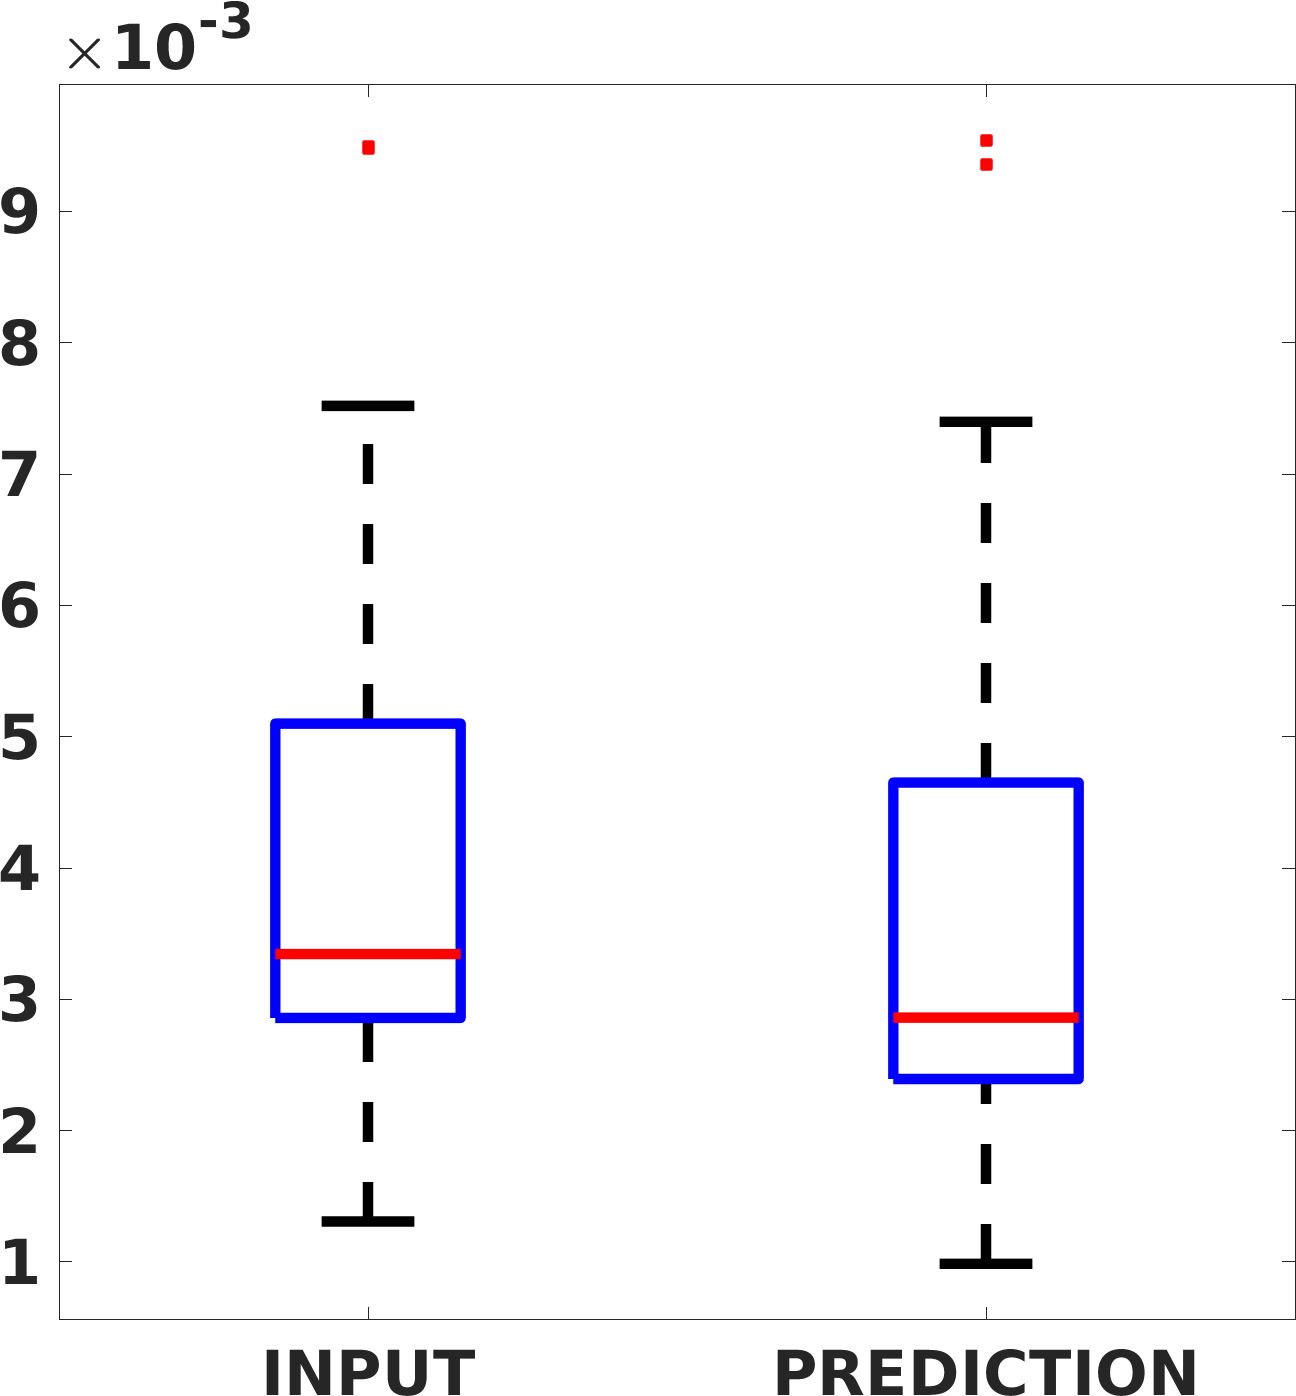

Fig. 8 shows the box plot of the SSIM (a-b-c, left) and MAE (a-b-c, right) quantitative metrics, as performed for PSNR metric. Also, these metrics show that our method improves the results of Cubic convolution both in terms of average value and variability. For example, the SSIM median value improves of on obstetric 4X images and the MAE median value improves of on cardiac 2X images.

Fig. 17 (left) shows the box plot of the quantitative metrics, comparing the target images with the prediction and the Cubic convolution, respectively. The PSNR metric is computed on a data set of 200 images, belonging to the same district, and with the same up-sampling factor. Analysing the obstetric anatomical district and concerning the corresponding raw images (Fig. 7 (a, left)), the denoising allows the network to significantly improve the results of the up-sampling and the prediction. In particular, comparing the target images with the predicted images, the median PSNR value of obstetric 2X denoised images is 51.8, compared to the median PSNR value of obstetric 2X raw images which is 36.9.

Fig. 17 (right) shows the histogram of the absolute value of the error with respect to the target, of the prediction and Cubic convolution respectively. This result shows that our framework increase of and (2X and 4X, respectively) the number of pixels where the prediction error is lower than 5, which is very similar to the target when visually analysing the images, and improved with respect to the learning framework applied to raw images. According to Fig. 18, our method improves the accuracy of Cubic convolution. For example, the SSIM increases of on cardiac 2X and the MAE increases of on abdominal 4X.